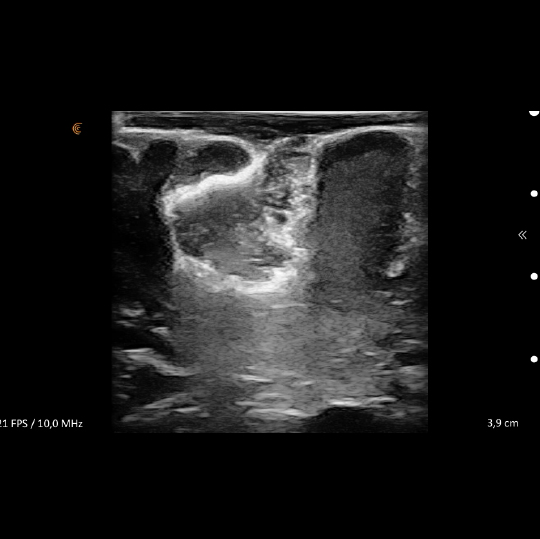

Donanım olarak nöronavigasyon (Şekil-1), Şekil 2a: İntraoperatif ultrason ile beyin tümörün görüntüsü.

Şekil 2b: ameliyat sonunda ultrason ile beyin tümörünün çıktığı görülüyor. intraoperatif ultrason ( Şekil-2 a,b) mikroskop altında yapılan mikrocerrahinin başarısını artırıyor. Eğer siz veya bir yakınınız beyin tümörü tanısı aldıysa, filmlerinizi değerlendirmek ve tedavi seçeneklerini konuşmak için kliniğimize başvurabilirsiniz.